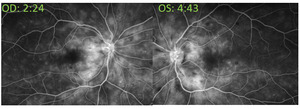

At the retina consultation, 4 days after initial presentation, visual acuity was 20/20 right eye and 20/20-1 left eye, and the patient subjectively felt her vision was improving. Intraocular pressures were 14 mm Hg right eye and 12 mm Hg left eye when measured by tonopen (with 95% confidence). Anterior and posterior segments were unchanged. Optical coherence tomography of the macula was performed and revealed resolution of the intraretinal fluid and resolving subretinal fluid in both eyes (Figure 2). Fluorescein angiography was performed and revealed normal transit time with mild leakage of both eyes without macular edema or hyperfluorescence of the optic disc. There were no distinct areas of nonperfusion in either eye. Both eyes showed engorged and mildly tortuous veins (Figure 4).